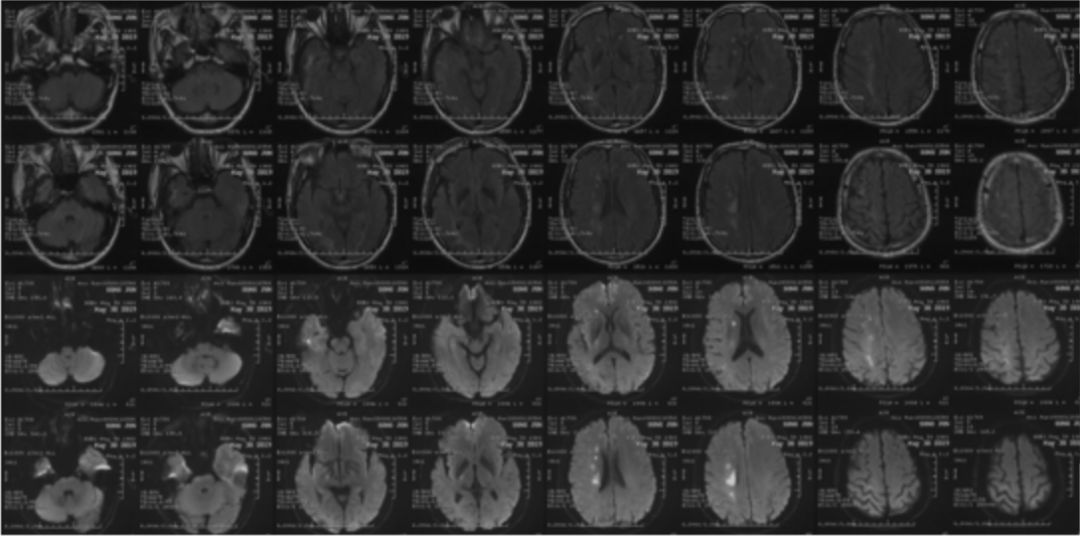

2019-05-24外院头颅MRI+MRA+DWI:右侧基底节区、放射冠、半卵圆中心脑梗死,右侧颈内动脉闭塞(图1)。

2019-07-05北京军颐中医医院高分辨核磁:

1.右侧颈内动脉夹层形成并血栓形成、管腔闭塞。

2.左侧颈内动脉眼段管腔中度狭窄,局部夹层不排除。

3.右侧大脑中动脉起始部管壁增厚,管腔重度狭窄(图3)。

2019-07-20外院PWI:右侧额颞叶灌注信号减低(图4)。